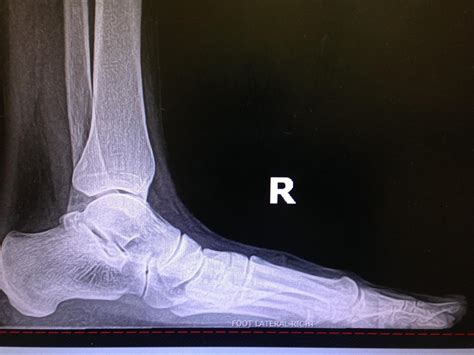

Pes Planus - Clinical Tree

Pes Planus - Clinical Tree